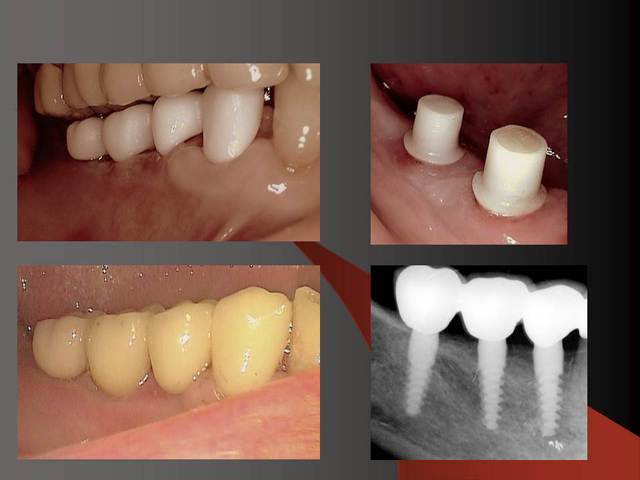

J'utilise la zircone depuis 7-8 ans,et je trouve que oui, la gencive est belle autour.

Par contre dans le dernier cas, je ne trouve pas que la gencive est belle, ell semble plutot inflammée...je crois que l'espace biologique n'est pas respecté.

Je trouve les implants sympas, mais pastrop l'aspect prothétique, mais c'est juste mon impression.

J´ai mis des photos pour mieux voir....

je vais ajouter des autres photos ( c´est mieux pour moi de expliquer avec des photos... :-))